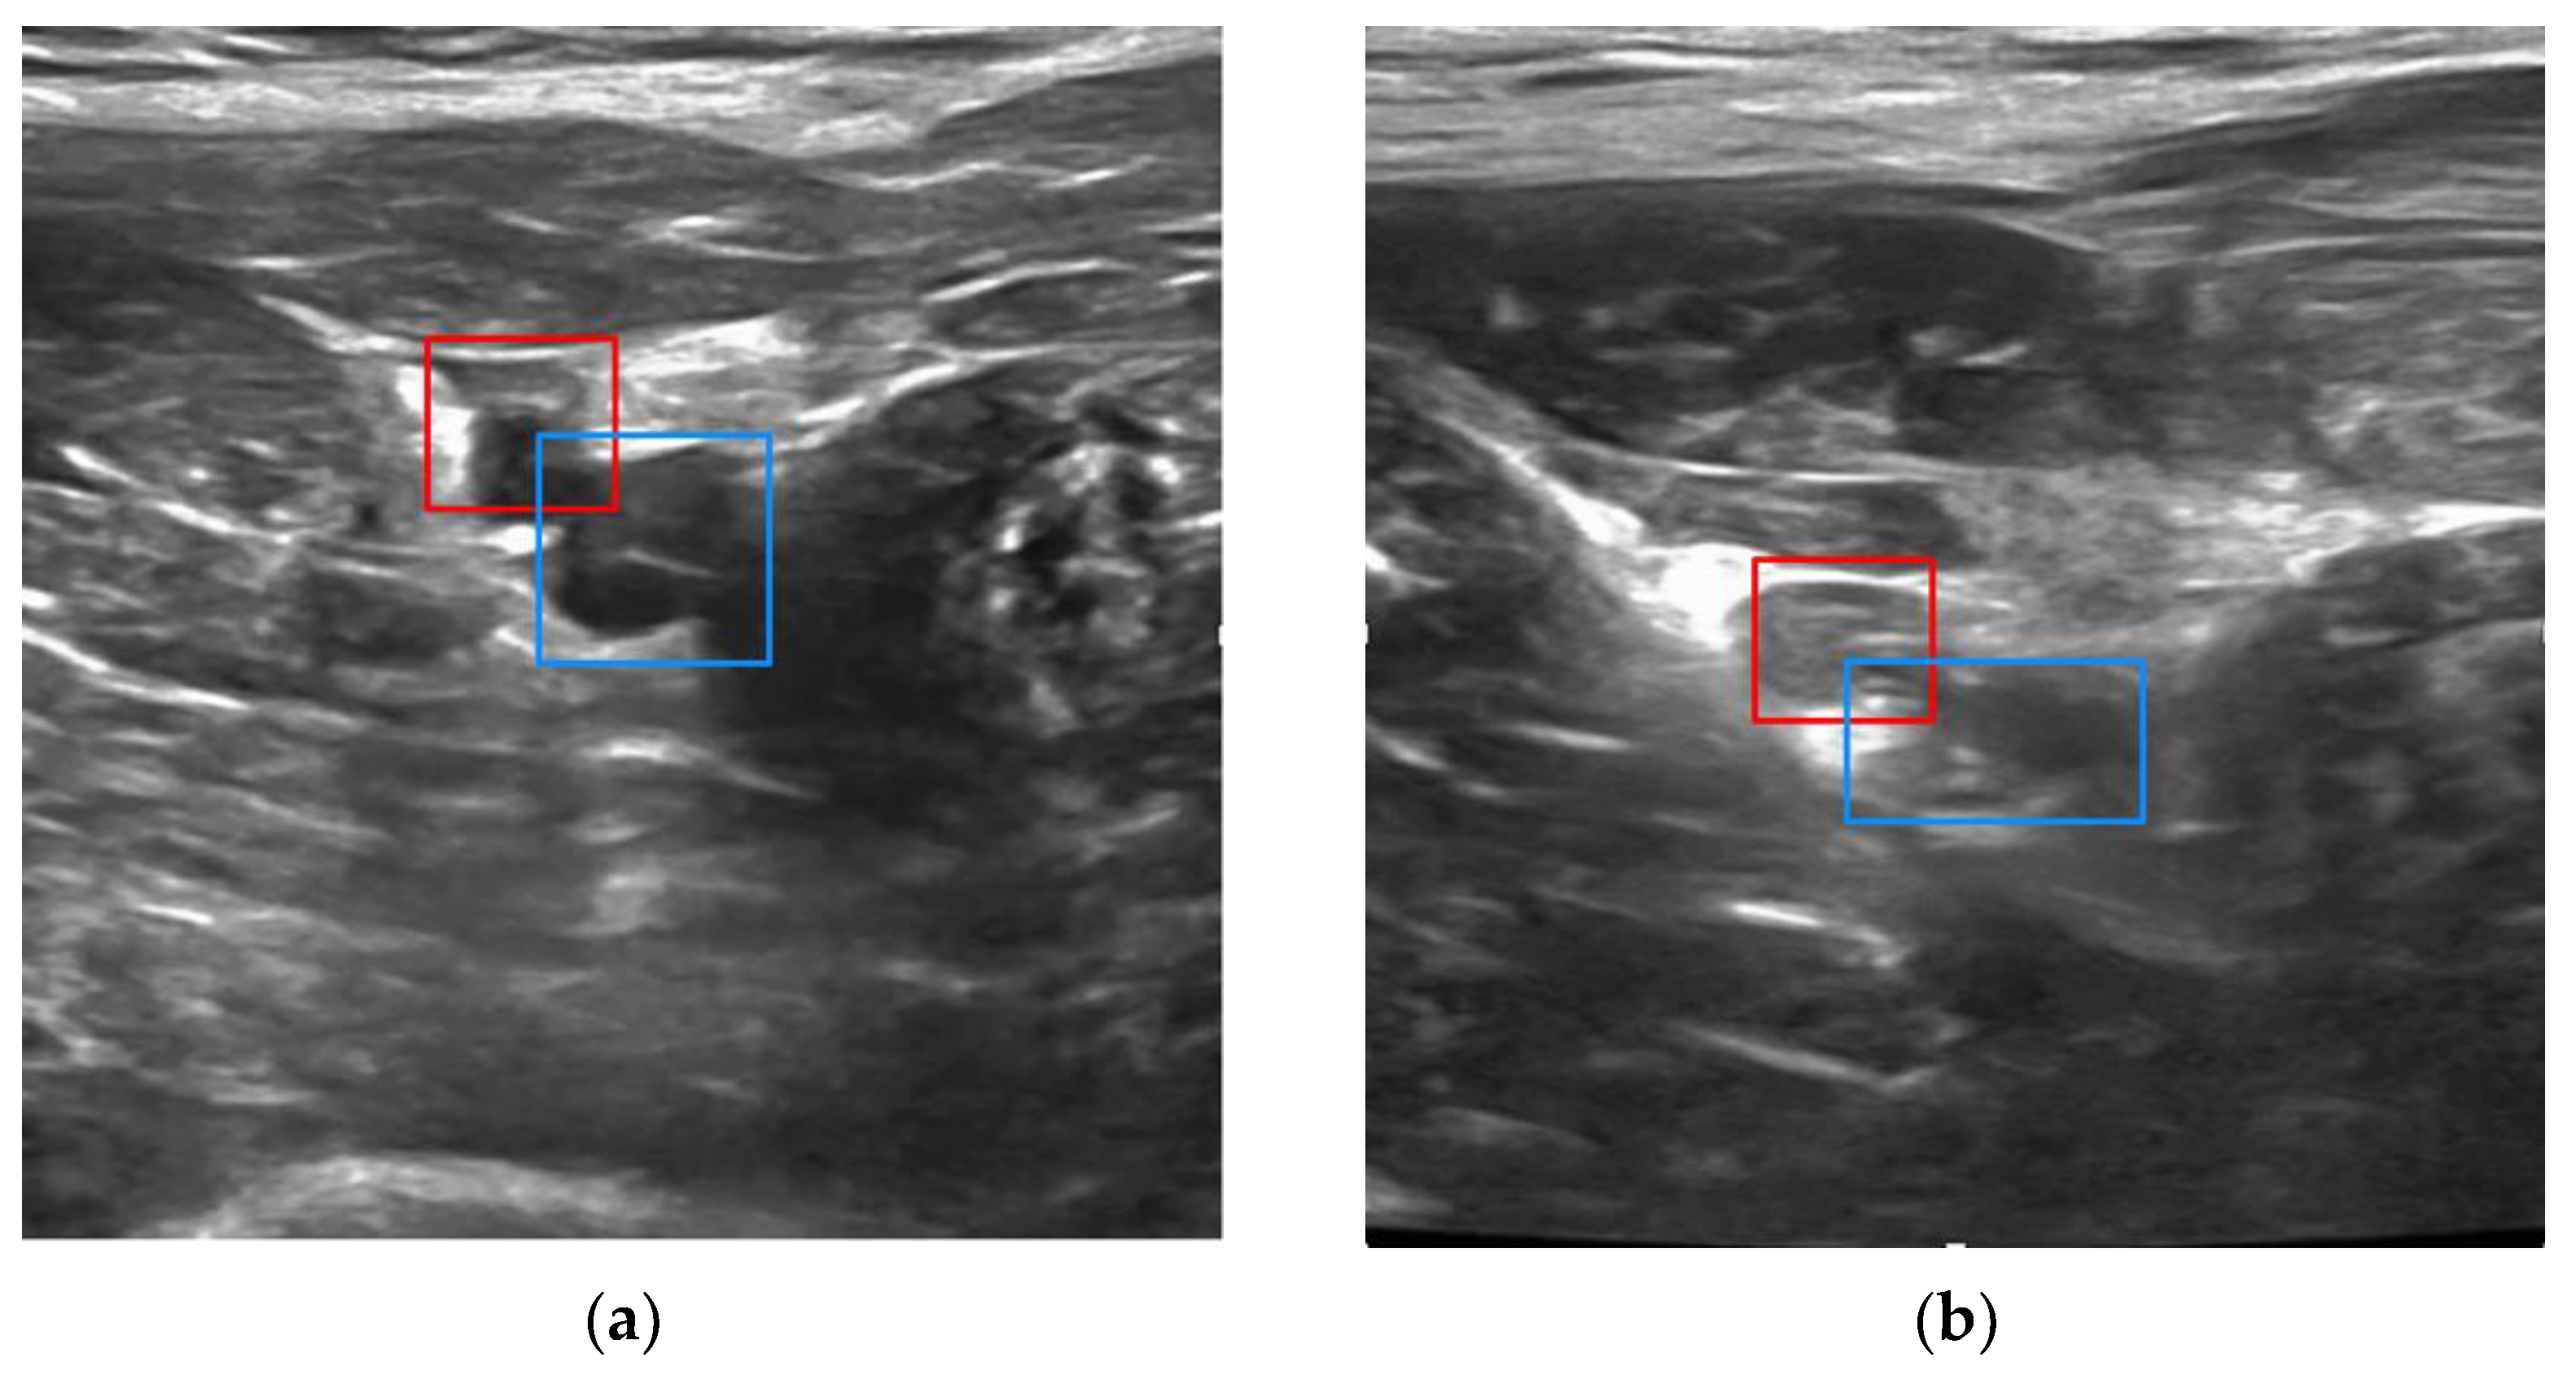

Examples of vessel detection and classification, and bounding box detection are shown for the right leg in Figure 6. (In the left leg, the artery would appear to the right of the vein in the ultrasound image.) To distinguish the artery from the vein, the YOLO network was trained to use morphological information, which could include the thicker and more hyperechoic arterial walls and differences in vessel cross sections, rather than a priori knowledge of which extremity is imaged.

Figure 6. Examples of real-time vessel detection and classification, and bounding box placement in porcine study (femoral artery, red; femoral vein, blue) overlaid on ultrasound image: (a) normotensive condition and (b) hypotensive condition.